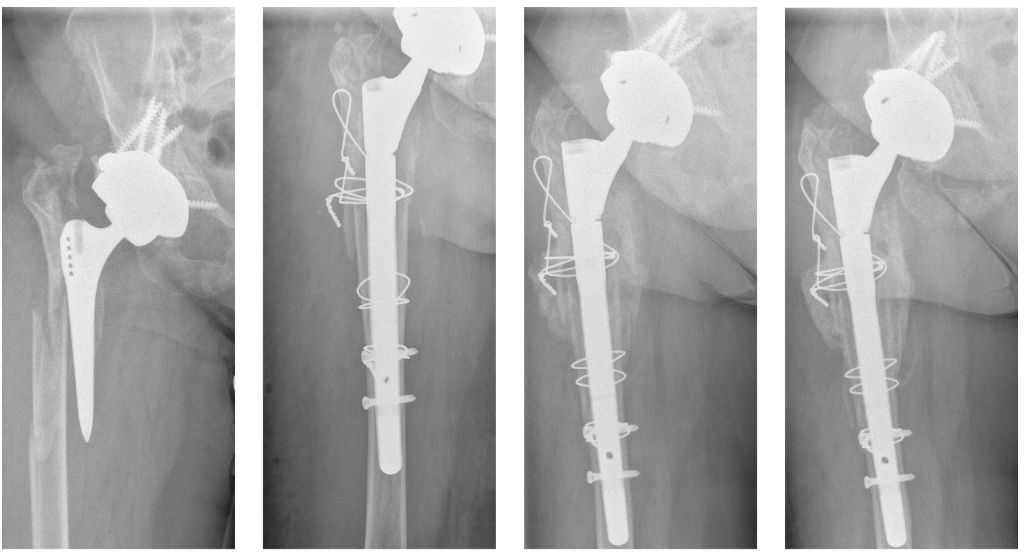

46 #Revision THA B3 with insufficient isthmus Cone-in-cone + distal interlocking at 4yrs 42 bony + 4 fibrous ingrowth stem The Bone & Joint Journal #hipreplacement buff.ly/5BOGCp5